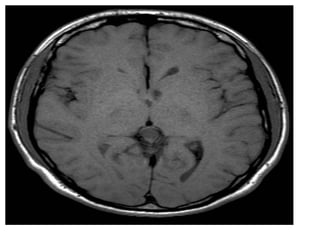

a)Sagittal T1 weighted MR

image shows an

heterogeneous pineal region

mass with foci of T1

shortening due to

hemorrhage , note the

associated hydrocephalus

b)Axial postcontrast T1-

weighted MR image shows

that the pineal region mass

also has an heterogeneous

enhancement with foci of

necrosis/cyst , involvement of

the tectal plate and both

thalami are also present (not

shown) , evaluation of serum

oncoproteins demonstrated

high level of b-hCG , biopsy of

the lesion revealed that it

corresponds to

Choriocarcinoma